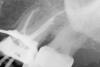

Снежана Опубликовано 24 октября, 2010 Поделиться Опубликовано 24 октября, 2010 http://i007.radikal.ru/1010/af/50d019699837.jpgвот здесь с большей долей вероятности есть мб2, остальные снимки ни о чем... на втором - стандартная укладка, вообще не разложен медиальный корень, про третий - можно с уверенностью сказать, что у пациента зубы есть) не более. На всех снимках не вошла в кадр периапикальная зона небного корня, поверните датчик вертикально. Ссылка на комментарий

x3m Опубликовано 24 октября, 2010 Поделиться Опубликовано 24 октября, 2010 вот здесь с большей долей вероятности есть мб2, +1сфоткать бы еще: тубус горизонтальнее и от пятерки - см. уровень раздвоения периодонтальной щели мез.корня Ссылка на комментарий

Len@ Опубликовано 24 октября, 2010 Автор Поделиться Опубликовано 24 октября, 2010 2-й и 3-й снимок это один и тот же зуб. Завтра попробую сделать мезиальную проекцию и заодно перепломбирую медиальный. Обычно в зеркале видно второе устье, а тут ничего. Ссылка на комментарий